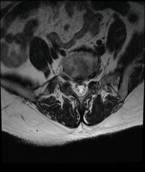

术前MRI检查

患者辗转于西安多家医院,被告知需进行手术治疗,因担心手术较大,出血多,后遗症多,迟迟不能决定手术。经别人推荐慕名找到我院骨科脊柱微创中心的张银刚教授。张银刚教授和刘凯博士等细致了解病情,仔细查体和阅片后分析:该患者腰5-骶1椎间隙退变严重,椎间隙变窄,腰5椎体失稳并向前滑脱,与增生的黄韧带和骨赘组织共同作用,造成腰椎管狭窄。进而引起腰痛、间歇性跛行等症状。

患者,女性,53岁。因患有“腰5椎体滑脱症、腰椎管狭窄症”被腰痛和跛行折磨多年,只能自主行走不到100米。日常生活质量和常规工作受很大影响。病情严重时只能卧床休息,连翻身都很困难。在当地医院查CT和磁共振显示:腰5椎体前滑脱、腰5-骶1节段腰椎管狭窄,黄韧带增厚,关节突关节增生。诊断为“腰5椎体峡部裂,滑脱 、腰椎管狭窄症”。